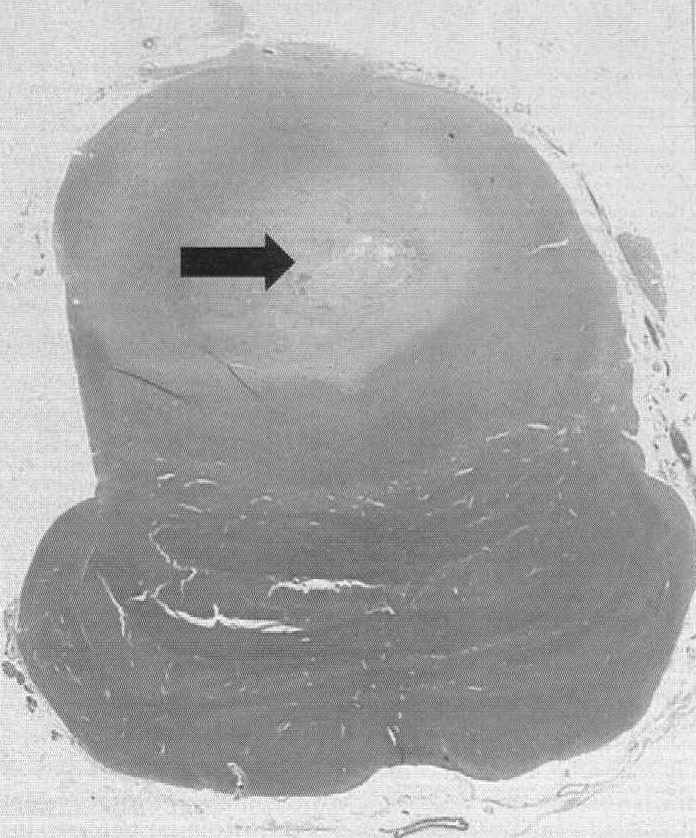

The "Sudden, Unexpected Death Related to Viral Myocarditis" discusses this very often difficult to diagnose condition. There are seventy-four references the most recent 2003.

The last chapter discusses "Subendocardial Hemorrhages" Again this is an arcane issue which is rarely discussed but is encountered from time to time in forensic cases. There are sixty-seven references the most recent is 2002.